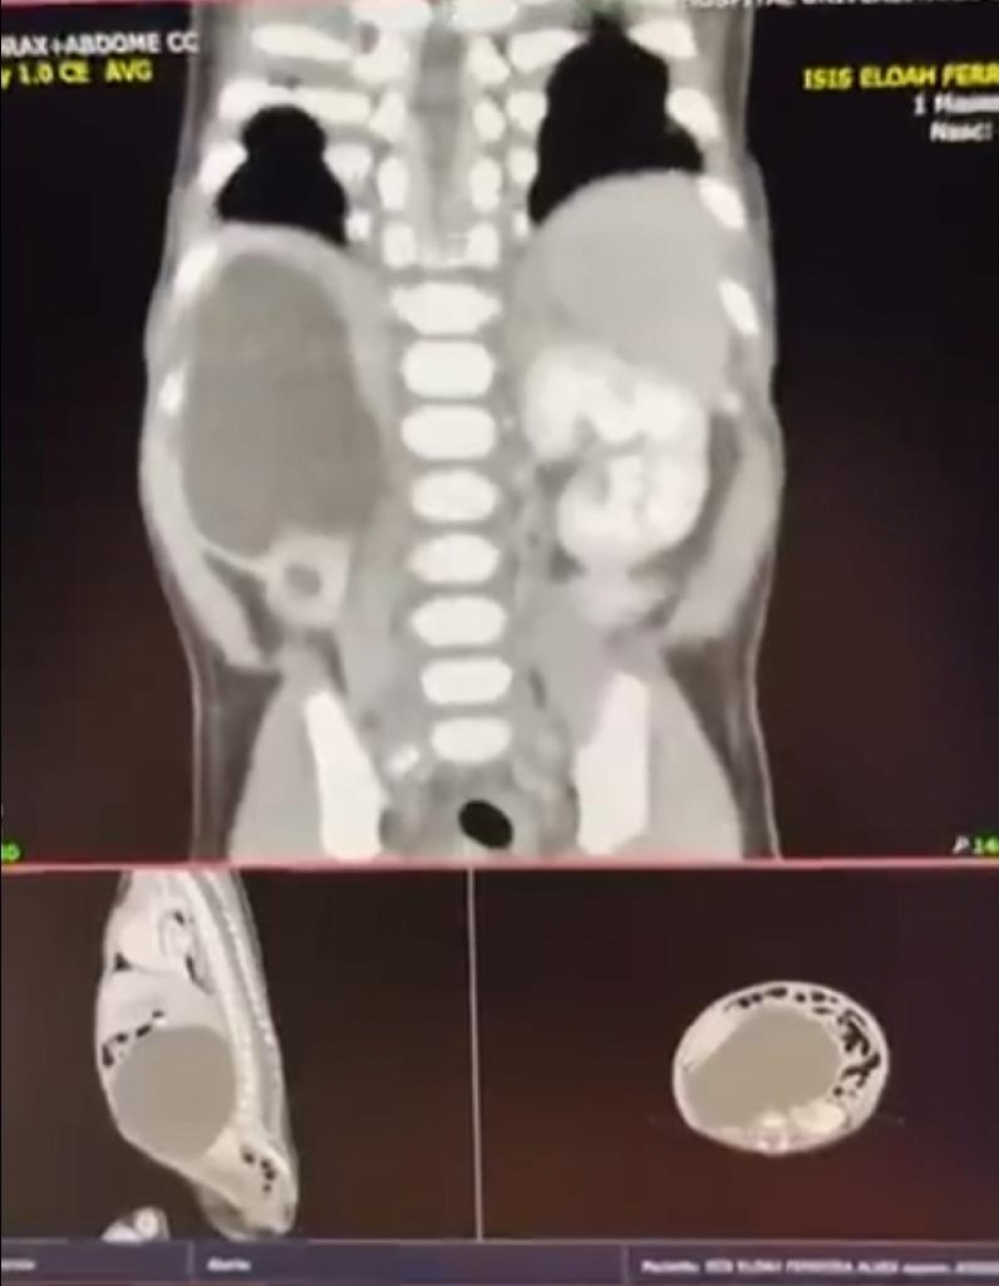

4 böyrəkli uşaq doğulub - FOTO

O, 4 böyrəklə doğulduğu üçün qızını unikal hesab edir. 21 yaşlı Thalia Silva Alves qadının dediyinə görə hamilə olarkən ona övladının böyrəyində problem olduğu deyilib. Körpə erkən doğulub və məlum olub ki, onun 4 böyrəyi var. Körpənin artıq orqanları5 ay sonra əməliyyatla götürülüb.